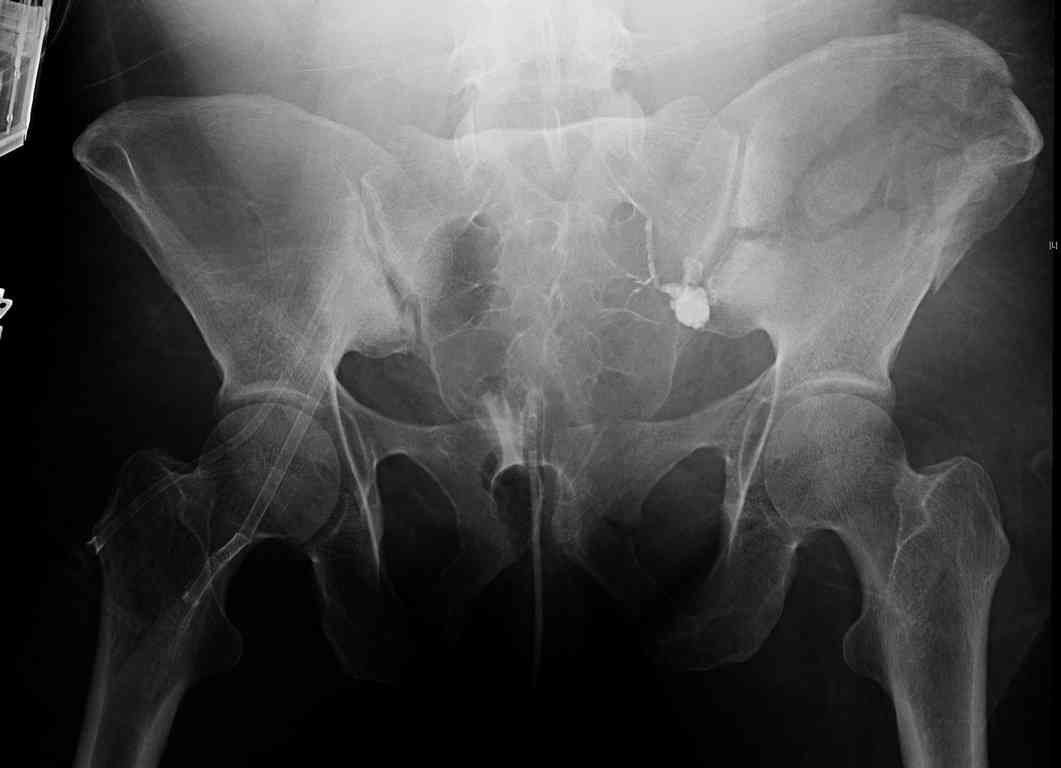

comminuted crescent fx

40 ish female ejected from car. Unstable, DPL negative, went to angio and had her pelvic bleeds embolized after many units of blood. GCS 6, floating elbow, clavicle, bothbones, etc.

My standard approach to this pelvis would be posterior, reduce/lag/plate thecrest, reduce/plate the caudal extent on the posterior crest and 1-2 lags back to front. In this case, the crest comminution seems to make plating all the way to the ASIS useless, as the plate would be on free floating fragments. Would plating the posterior extent of the fracture to secure the reduction at the SI joint and 2 screws back to front be sufficient fixation? Would anyone do a perc reduction and perc back to front screws, and would that be sufficient if the SI joint could be reduced (although I don't see how this could be accurately reduced closed). Would an ilioninguinal with a pelvic brim plate and posterior column screws be a better approach, although reducing the SI would be more indirect and less accurate?

It's a comminuted iliac fracture involving the GS notch and all that

implies...use the lateral interval of an ilioinguinal, sequentially reduce,

and fix...if you want to, you can attach the dominant unstable fragment to

both the stable posterior iliac fragment and also to the anterolateral portion of the sacrum using plates...if you choose to anchor to both, the implants get congested on the iliac side of the SI joint so be precise with contouring and such applications...perhaps and based on the images shown, an iliosacral screw would only augment the construct if applied to the second sacral segment (but this is difficult to assess on the images shown). The crest components can be held securely with screws and/or peripheral plating.